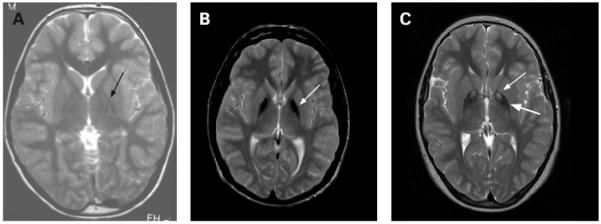

Рисунок 1. Т2-взвешенные снимки. А - здоровый пацент. В - идиопатическая NBIA, стрелкой обозначена зона гипоинтенсивности в медиальном бледном шаре. С - PKAN, регион гиперинтенсивности (тонкая стрелка) окружён гипоинтенсивной зоной (толстая стрелка), так же в медиальном бледном шаре, т.н "глаз тигра" - типичное для PKAN распределение железа.

В случае если речь идет о других формах заболевания из спектра, постановка диагноза может оказаться гораздо более затруднительной, чем при PKAN. В этом случае на помощь приходит МРТ, подходящая для первичного определения формы нейродегенерации, тем самым наталкивая врача на выбор правильного молекулярно-генетического исследования. МРТ головного мозга является стандартным методом исследования для описываемой группы заболеваний. Более новые нейровизуализационные технологии, например, магнитно-резонансная спектроскопия (МРС), предположительно, тоже могут оказаться полезными для постановки диагноза, однако на данный момент это достоверно неизвестно.

По определению в базальных ганглиях людей с NBIA определяется ненормально высокое количество железа. Обычно эти зоны определяются как гипоинтенсивные участки бледного шара и ретикулярной части черной субстанции на Т2-взвешенных снимках. На Т1-взвешенных снимках эти области изоинтенсивны, что помогает отличить их от отложений кальция и прочих изменений. При идиопатической нейродегенерации с накоплением железа участки его аккумуляции могут встречаться в красном ядре, зубчатом ядре, скорлупе и хвостатом ядре. После постановки диагноза проводить повторные исследования при помощи МРТ не имеет смысла. Следует помнить, что порой диагностика с целью выявления конкретной формы NBIA может занять несколько лет. Например, в случае болезни Куфора — Ракеба или PLAN накопление железа может произойти только в ряде случаев.